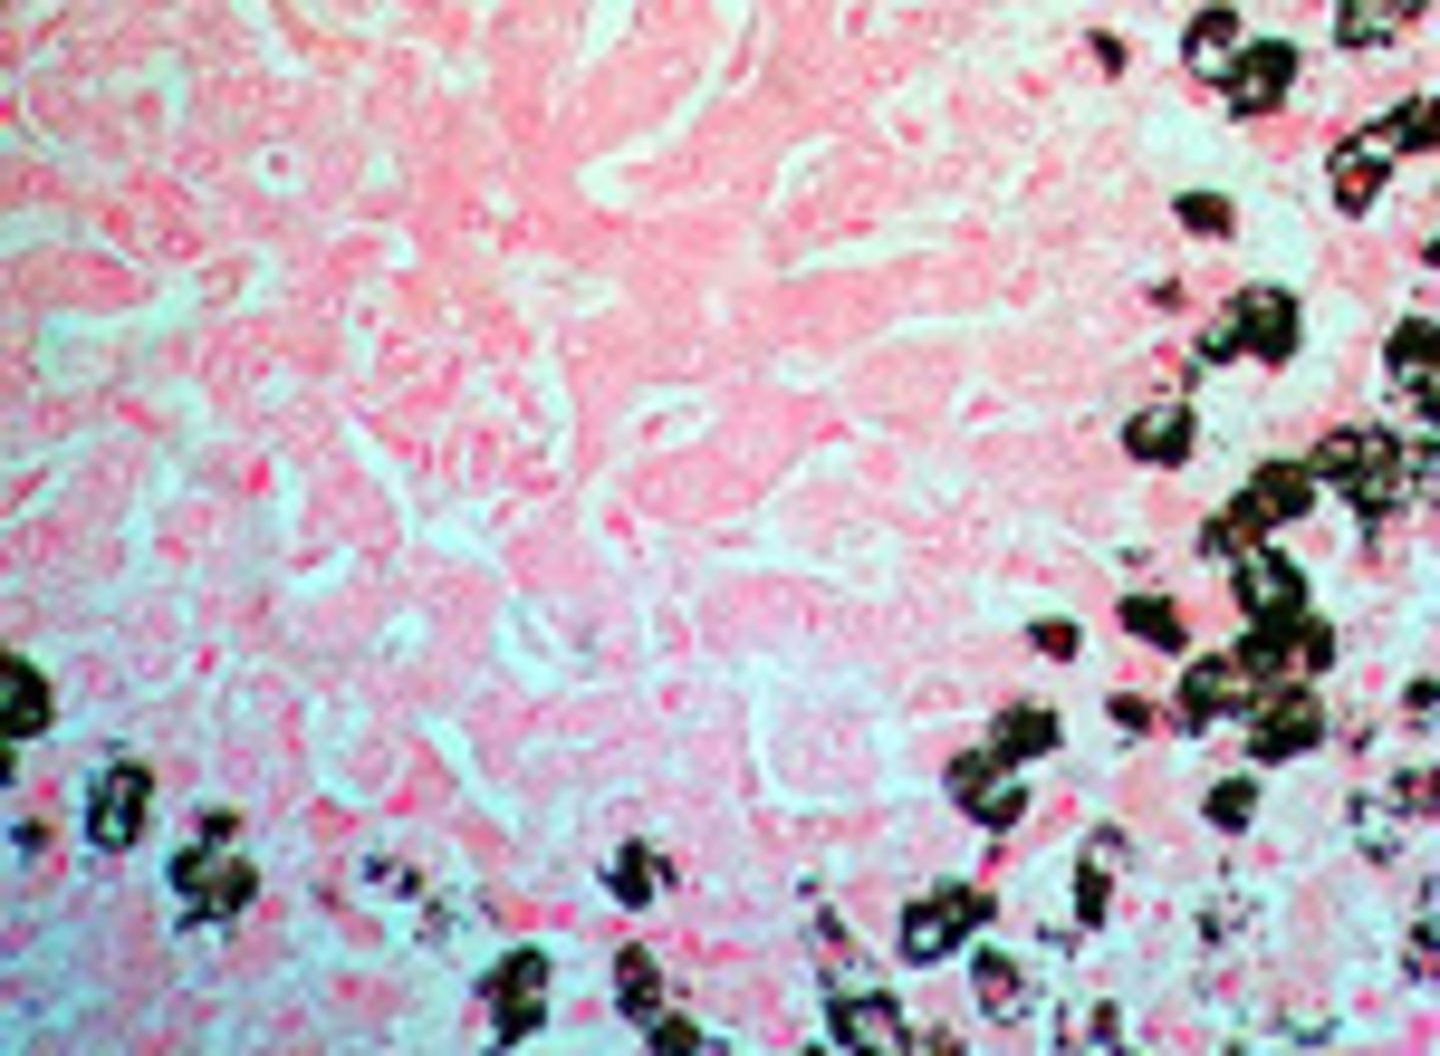

What does Ziehl-Neelsen/Fite-Faraco stain?

acid fast bacteria; Mycobacterium and Nocardia